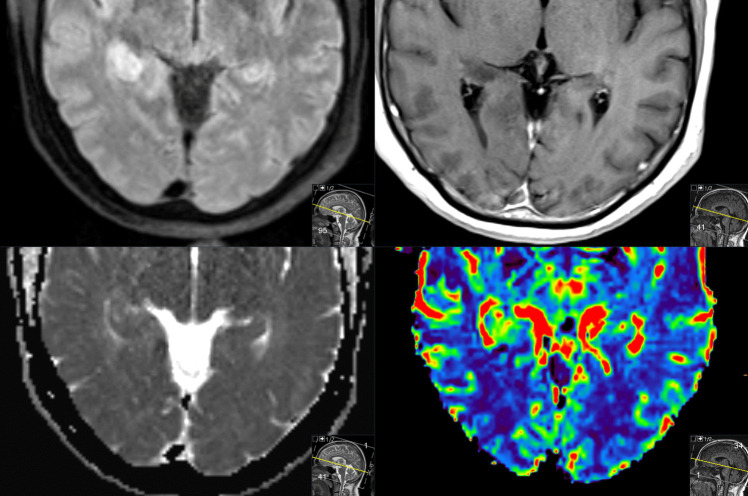

Abstract Image